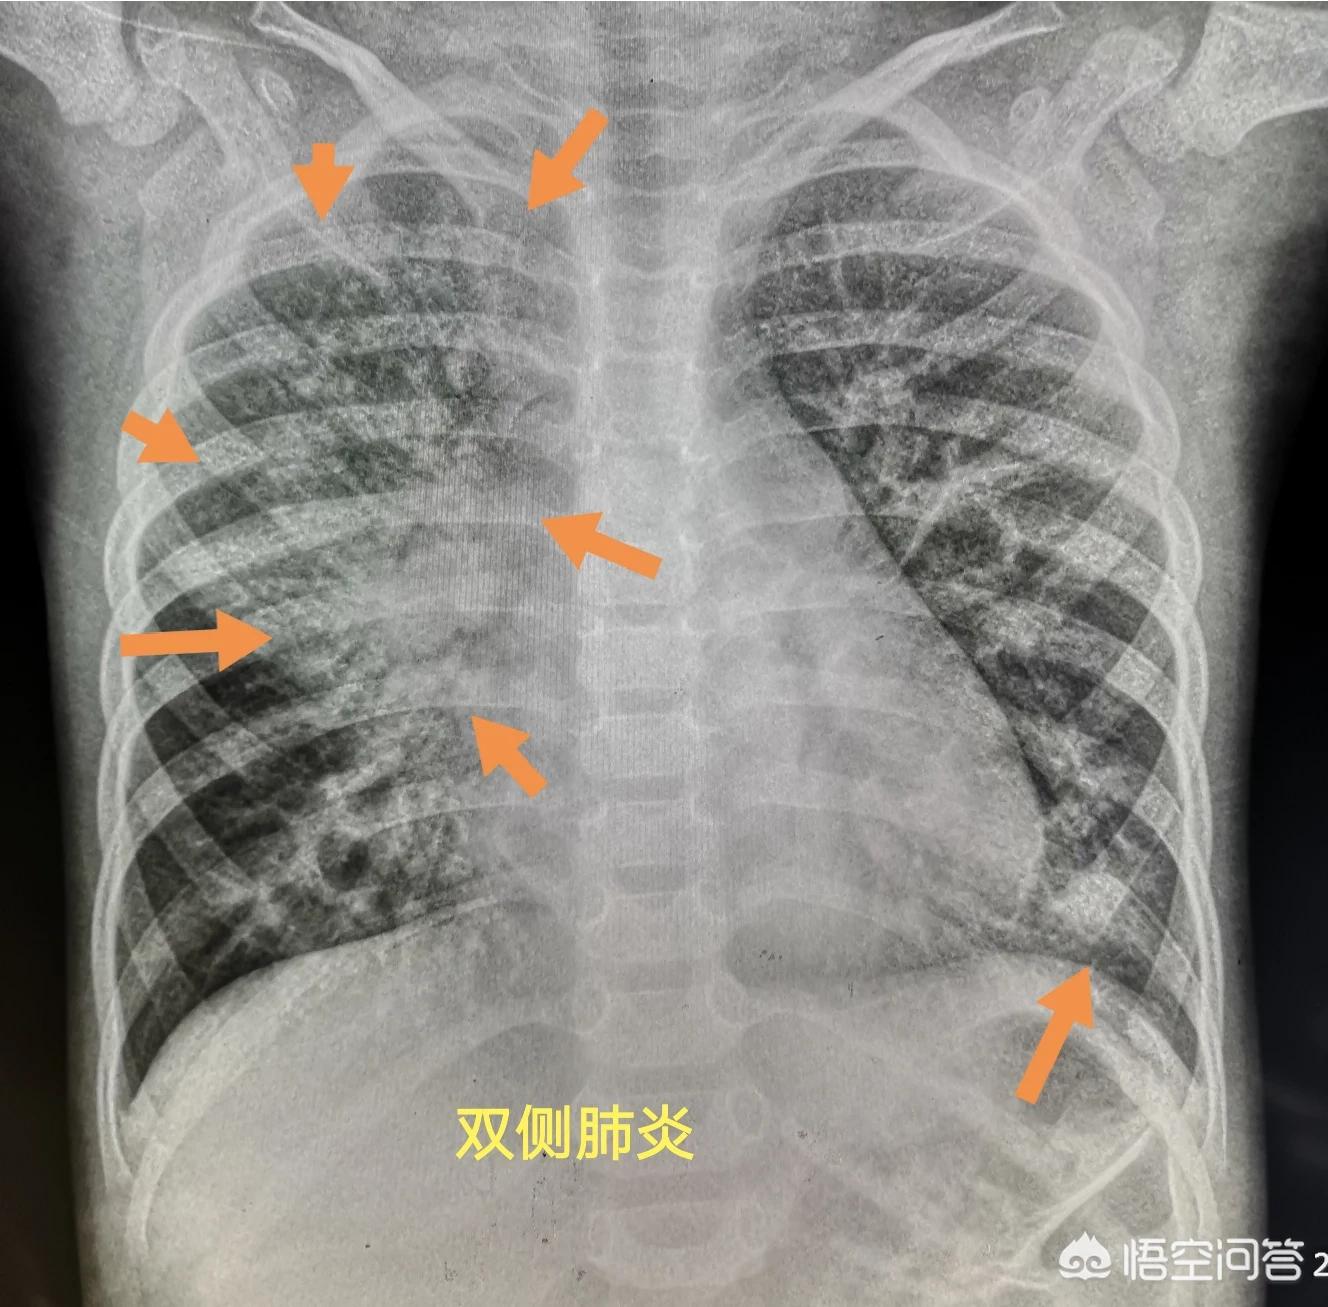

这个小女孩感冒好几天了,咳嗽越来越厉害,有时甚至能引起呕吐,但只是发热一天。

拍胸片发现左侧肺炎已经很明显了(片子上看到大片雾蒙蒙的实变影,提示病程在一周左右),需要马上抗生素治疗。

孩子的妈妈还念叨一句,一直以为只要不发热就没事,昨天开始发热,才有点担心。

好在治疗挺及时,使用的抗生素也很敏感,六天以后复查炎症已经基本吸收了: